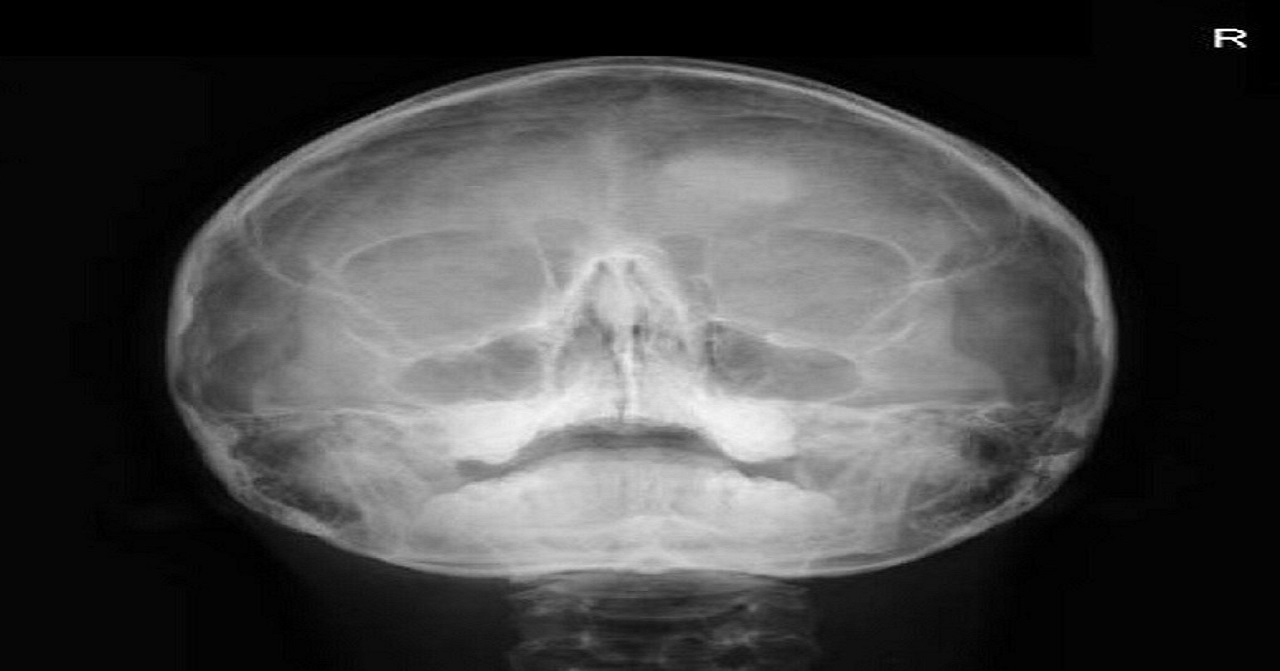

P.A. (Posteroanterior)

Radiografía frontal utilizada para observar cambios en la dimensión media o lateral del cráneo, senos frontales, fosas nasales, orbitas, mandíbula, senos etmoidales y traumatismos maxilofaciales.